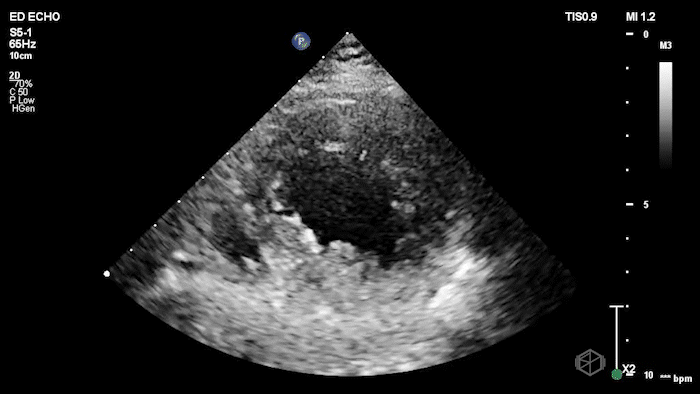

They were examining a 30’s female who was presenting to the ED with headaches for multiple years and had some vision disturbances. The performed an ocular POCUS that demonstrated the following:

The POCUS shows optic nerve edema right (0.793cm) greater than left (0.71cm) with bilateral papilledema. There may also be a faint vitreous detachment of the right eye. There was concerned for increased intracranial pressure.

The patient had an MRI brain and orbits that showed, “intraocular protrusion of the right greater than left optic nerve heads with increased prominence of the CSF spaces of the bilateral optic nerve sheaths, can be seen in a idiopathic intracranial hypertension.” She had a lumbar puncture that had elevated opening pressure and was started on acetazolamide.

Diagnosis: Bilateral optic nerve edema/papilledema and idiopathic intracranial hypertension

ONSD measurements in this case are markedly abnormal. The optic nerve sheath diameter (ONSD) is measured 3 mm posterior to the globe. In adults, an ONSD > 5.0 mm is generally considered abnormal; values > 6.0 mm are strongly associated with raised intracranial pressure (ICP). Bilateral measurements of 7.9 mm (right) and 7.1 mm (left) are consistent with elevated ICP. The probe should be held lightly with ample gel to avoid artifactual compression (📚 PMID: 18509619, 18275454)

Ocular ultrasound demonstrates strong diagnostic performance for raised ICP. Meta-analyses show high accuracy: pooled estimates around ~90% sensitivity and ~80–90% specificity, with performance varying by cutoff and population; ONSD should be used as an adjunct to clinical assessment and neuroimaging. (📚 PMID: 21505900, 30019201)

Papilledema may lag behind acute ICP elevation. ONSD can enlarge rapidly with ICP rise, whereas fundoscopic papilledema often develops later (typically ≥24 hours and usually within ~7 days). Absence of papilledema does not exclude early intracranial hypertension. (📚 PMID: 35698673)

Point-of-care US measurement of optic disc elevation/height helps when fundoscopy is limited. Studies report cutoffs from ~0.6–1.0 mm: ≥1.0 mm is highly specific for papilledema in ED cohorts; lower cutoffs (≈0.6–0.7 mm) improve sensitivity. (📚 PMID: 24050798, 37227512)